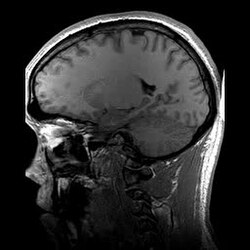

MRI stands for Magnetic Resonance Imaging. It is a special kind of medical test that helps doctors look inside your body. During an MRI, a big magnet and radio waves are used to take pictures of the inside of your body. The MRI machine is like a big tube that you lie down inside. The magnet makes your body's atoms send out signals, and the computer in the MRI machine reads the signals and turns them into pictures. Doctors look at these pictures to see if there is something wrong inside of your body.